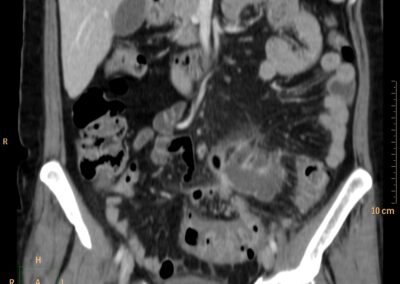

ΕΚΚΟΛΠΩΜΑΤΑ ΠΑΧΕΟΣ ΕΝΤΕΡΟΥ Posted by ΙΠΠΟΚΡΑΤΕΙΟ ΙΩΑΝΝΙΝΩΝ | Dec 16, 2020 | ΠΕΠΤΙΚΟ | 0 ΚΛΙΝΙΚΑ ΣΤΟΙΧΕΙΑ – ΙΣΤΟΡΙΚΟ υποτροπιάζοντες επαναλαμβανόμενοι πυρετοί κυρίως απογευματινές ώρες ΕΡΓΑΣΤΗΡΙΑΚΟΣ ΕΛΕΓΧΟΣ ΑΠΕΙΚΟΝΙΣΤΙΚΟΣ ΕΛΕΓΧΟΣ διακρίνονται τα αποστήματα στην ελάσσονα πύελο, καθώς και εκκολπώματα με εικόνα πάχυνσης του τοιχώματος του σιγμοειδούς ΣΥΖΗΤΗΣΗ